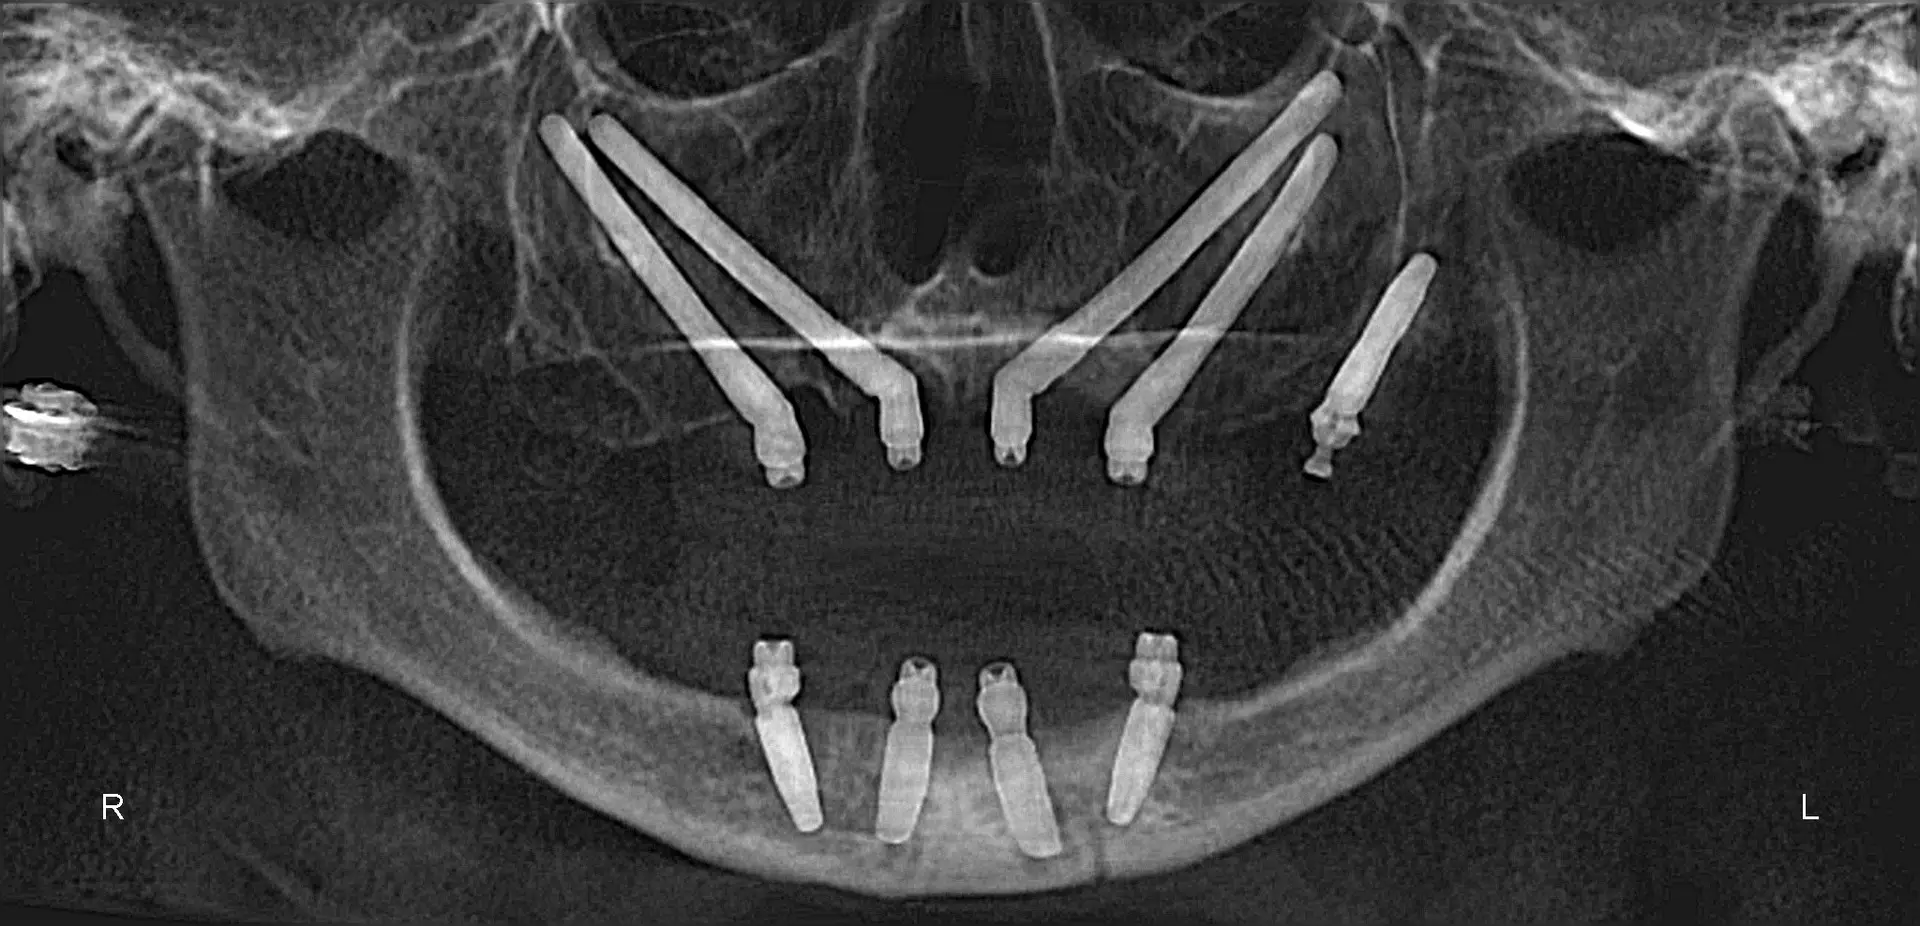

Documented case of Ana, a patient presenting with severe bone loss and failed implants. She was treated by our faculty member, Dr. Jay Neugarten, during the ZAGA Course as part of a live surgical demonstration for course participants. Treatment involved quad zygomatic implants and one pterygoid implant to improve stability. Using the ZAGA Approach, we were able to successfully rehabilitate the case despite the previous implant failures and deliver an immediate prosthesis on the same day as surgery. This case represents part of the clinical education and knowledge participants gain during the ZAGA course.